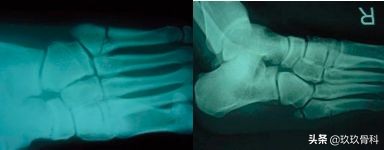

辅助检查

- X线 踝关节正侧位(必要时应加照踝穴位)

应力位片

第五跖骨疲劳骨折